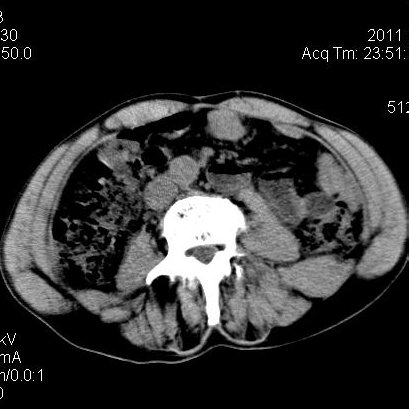

肝左叶发育异常

男性,55岁,骑摩托车摔倒后入院,自述右上腹疼痛

[backcolor=#FF0000]第一次诊断的时候也是这么肯定,可是床旁超声检查并没有发现明显异常,而且患者的一般症状都良好。还好临床只是保守治疗,没有立即手术,第二次复查的时候没有一点变化,又做了MRI检查,没有血肿,

这是一例肝左叶发育异常的,很个性吧~[/backcolor]